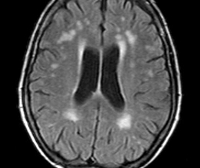

Внутричерепная гипотензия: КТ-исследования и их интерпретация

Раздел: Образы вокруг